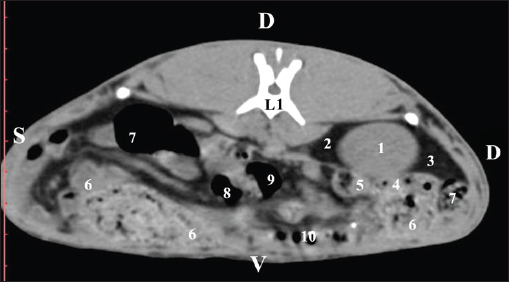

Fig. 1. Pre-contrast computed tomography (CT) anatomical scan of the regio abdominis cranialis at the Th13 level. (1) Lobus hepatis dexter; (2) ren dexter; (3) lobus caudatus (proc. caudatus) with visceral adipose tissue; (4) pars descendens of the duodenum; (5) ileum; (6) gl. adrenalis dextra; (7) colon ascendens; (8) cecum; (9) colon transversum; (10) colon descendens; (*) 13th rib. At the next scan level (L1), the normoattenuated image of the right kidney was more detailed and in contact with the lobus hepatis dexter, lobus caudatus, duodenal pars descendens, and ileum. The cortex renis and medulla renis were not clearly differentiated. Pelvis renalis appeared as a linear hypoattenuated finding against the relatively normoattenuated kidney cortex and medulla. The proximal part of the ureter was seen medial to the right kidney (Figs. 2 and 3).

Fig. 2. Pre-contrast computed tomography (CT) anatomical scan of the regio abdominis cranialis at the L1 level. (1) Ren dexter; (2) lobus hepatis dexter; (3) lobus caudatus (proc. caudatus) with visceral adipose tissue; (4) pars descendens of the duodenum; (5) ileum; (6) cecum; (7) colon ascendens; (8) colon transversum; (9) colon descendens; (10) jejunum.

Fig. 3. Pre-contrast computed tomography (CT) anatomical scan of regio abdominis cranialis at the L1 level. (1) Medulla renis; (2) cortex renis; (3) pelvis renalis; (4) lobus caudatus (proc. caudatus) with visceral adipose tissue; (5) ureter; (6) pars descendens of the duodenum; (7) jejunum; (8) cecum; (9) colon ascendens; (10) lien; (11) colon descendens; (12) colon transversum. At the L2 level, the right kidney was in contact with the liver’s proc. caudatus, pars descendens of the duodenum, and the ileum. Pelvis renalis was a distinct hypoattenuated funnel-shaped soft tissue finding, whose narrow end pointed at the renal hilum and passed into the ureter. Recessus renalis was a clearly visible hypoattenuated widening of the central part of the renal pelvis in the dorsal and ventral directions (Figs. 4 and 5).